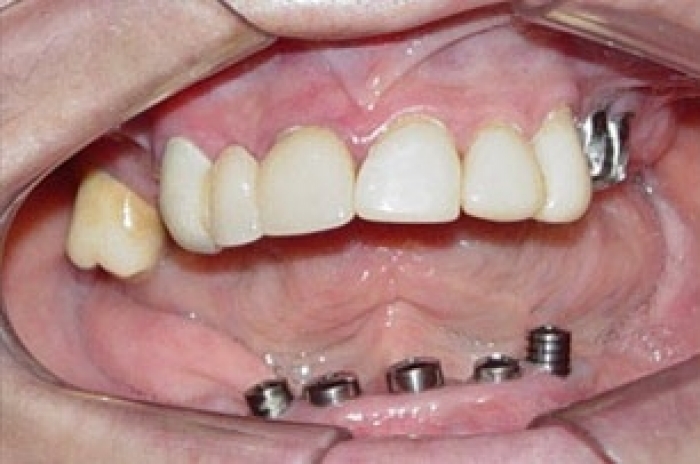

Imagem inicial